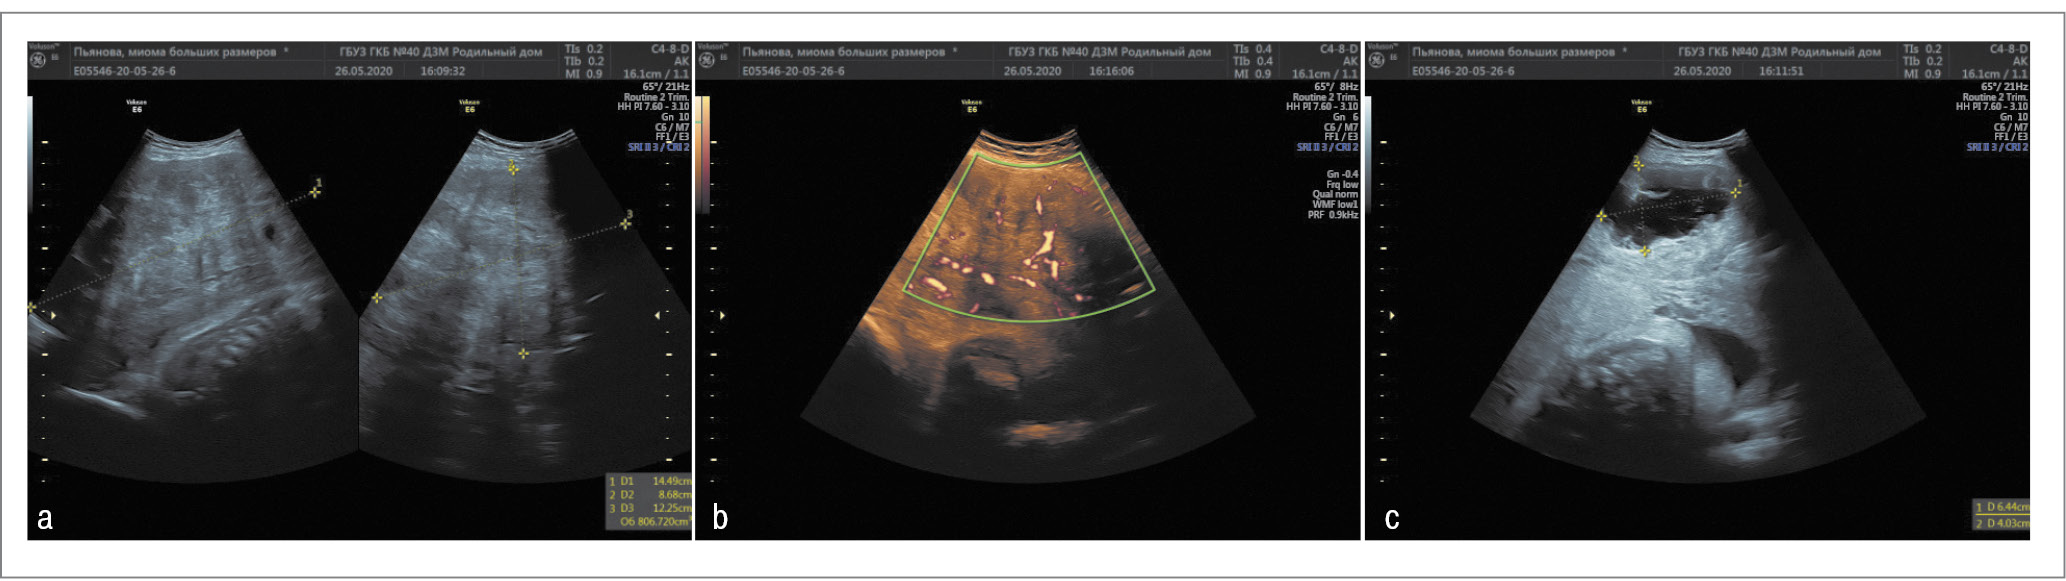

В 30 нед беременности размеры узла составили 162×98×123 мм (объем – 998 см3), кистозная полость уменьшилась до 70×74 мм, а содержимое приобрело анэхогенный характер. В 34 нед миоматозный узел уменьшился до размеров 144×86×122 мм (объем – 810 см3), кистозная полость уменьшилась до 64×40 мм (рис. 3).

Рис. 3. ММ в 34 нед беременности: а – миоматозный узел; b – ЦДК в узле; c – кистозные полости в узле. / Fig. 3. UF at 34 weeks of pregnancy: a – myomatous node; b – CFM in the node; c – cystic cavities in the node.